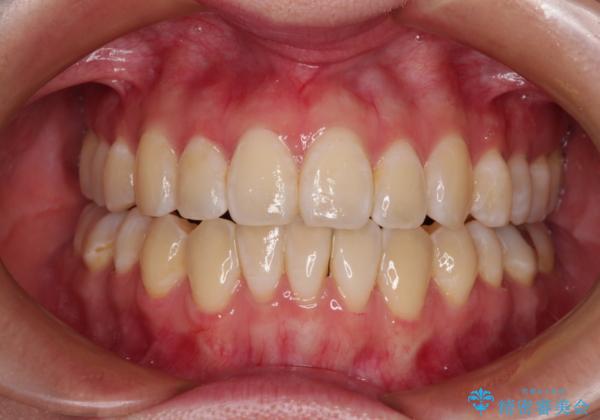

外に飛び出して磨きにくい奥歯と上下前歯の隙間 インビザラインによる矯正治療

下顎前歯の1本欠損により左右の咬合が不安定となり、治療経過で噛みにくい状態が続きましたが、最終的には違和感なく噛めるようになりました。